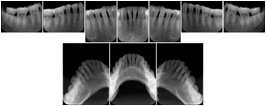

Intra-oral radiography typically involves acquisition of multiple images of various parts of the dentition. Many digital radiographic systems offer customized templates that are used for displaying the images in a study on the screen. These templates may also be referred to as mounts or view sets. The Structured Display Object represents a standard method of encoding and exchanging the layout and intended display of Structured Displays. A structured display object created in this manner could be stored with a study and exchanged with images to allow for complete reproduction of the original exam.

1. A patient visits a General Dentist where a Full Mouth Series Exam with 18 images is acquired. The dentist observes severe bone loss and refers the patient to a Periodontist. The 18 images from the Full Mouth Series along with a Structured Display are copied to a DICOM Interchange CD and sent with the patient to see the specialist. The Periodontist uses the CD to open the exam in his Dental Radiographic Software and consults via phone with the General Dentist. Both are able to observe the same exam showing the images on each user's display using the exact same layout.

Intra-oral Full Mouth Series Structured Display

Figure OO-1. Intra-oral Full Mouth Series Structured Display